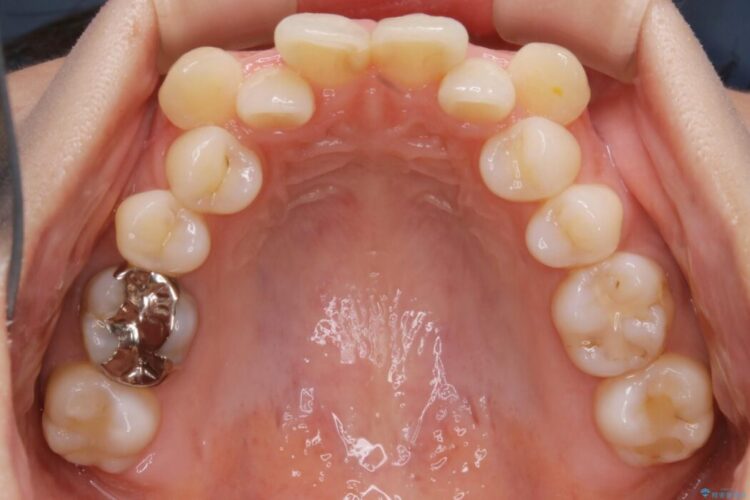

左右の奥歯が前方に寄っていることにより八重歯の発生や重度の叢生に繋がっていました。

ですが詳しく検査をしたところ、左右の奥歯の前後位置に関してはズレが少ない状態でした。

加えて患者様の顎の大きさに対する歯の数が多いことが叢生の原因になっていることから、抜歯した上で歯列を整えるほうが最終的な仕上がりとして良い結果になると判断しました。

まず噛み合わせに問題が少ない奥歯の位置を極力変えないように上下左右4番目の歯を抜歯することで歯列矯正のためのスペースを確保し、空いた隙間で前歯の凹凸をきれいに並べていくこととしました。